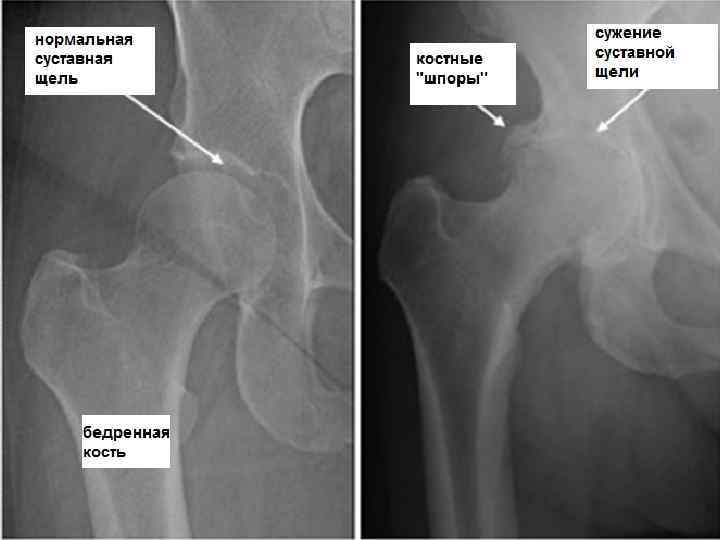

Коксартроз 1 -й степени характеризуется слабой ноющей болью в области тазобедренного сустава, усиливающейся во время ходьбы и других движений. При снятии нагрузки болевые ощущения прекращаются. Человек способен совершать непродолжительные прогулки, но без отягощений. Суставная щель на рентгеновском снимке немного сужена, что, впрочем, некритично для относительно свободных движений бедра.

Коксартроз 2 -й степени сопровождается сильными болевыми ощущениями, которые зачастую носят хронический характер, и пациент вынужден принимать обезболивающие. Контрактура не позволяет человеку ходить на дальние расстояния, а позднее приковывает к постели инвалидному креслу. Нередко больные жалуются на крепитацию (скрипящие или хрустящие звуки в суставе). Нога со стороны поражённого ТБС зрительно укорачивается по причине перекоса таза. На рентгеновском снимке явно видна деформация бедренной головки. • Коксартроз 3 -й степени выражается в полном смыкании краёв суставной щели, приводящем к абсолютной контрактуре. Пациент испытывает болевые ощущения не только при нагрузке на сочленение, но и без неё. На данной стадии наблюдается сильная крепитация. По всему суставу образуются склеротические участки.